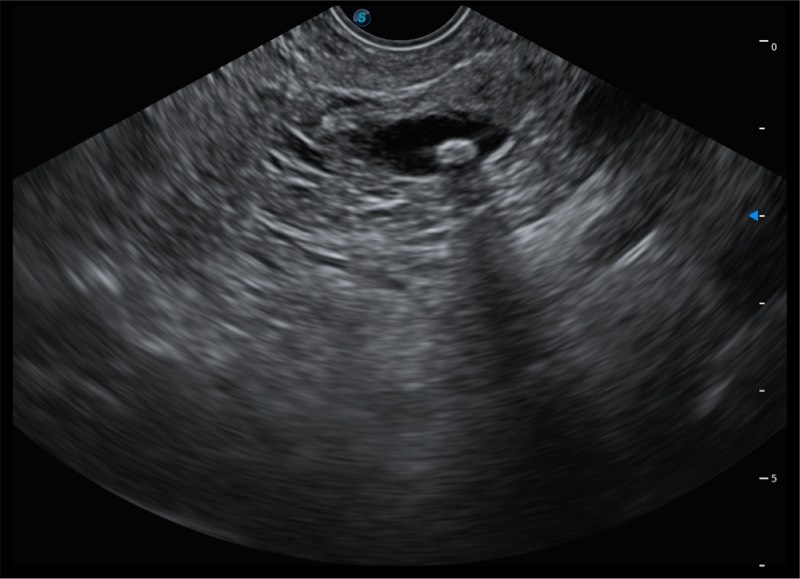

150°超声扫描角度